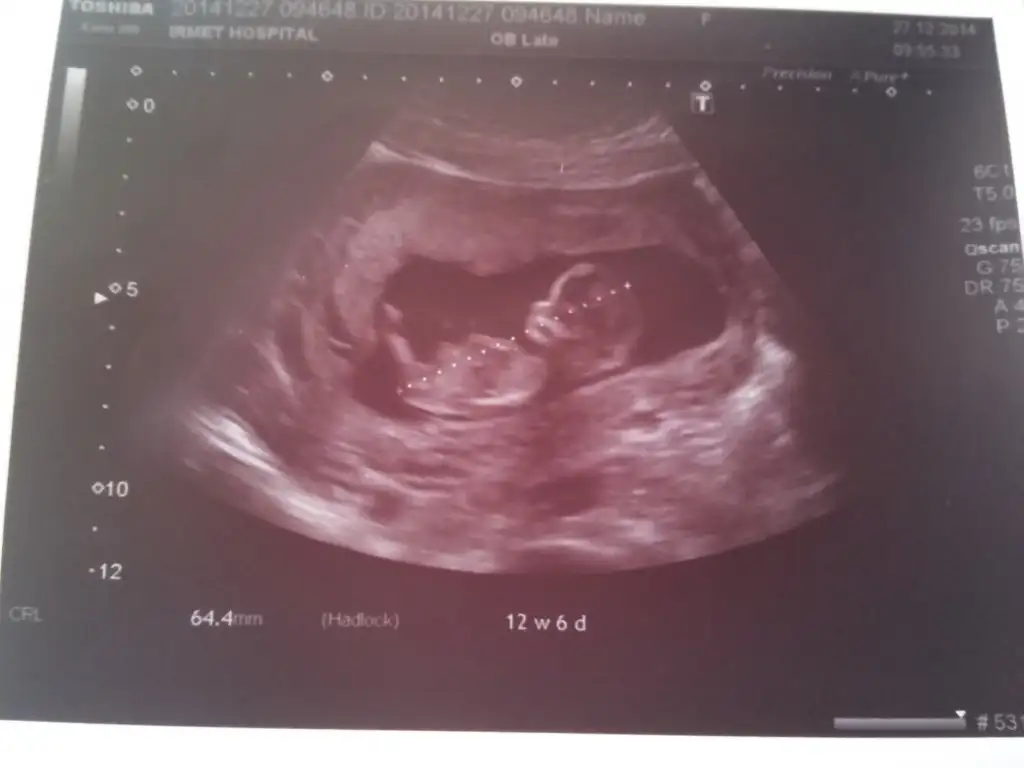

Merhaba hanımlar herkeze hayırlı gebelik diliyorum benim yavrumada bakarmısınız ablaları teyzeleri 12. Haftaya girdik

image.webp

İlk iki resim 12+3 , diğer ikisi 12+6

Malesef resimler biraz önden. İlk resimlerde tam çekip, ikincilerinde yaklaştırıp screenshot yapıp ekledim.